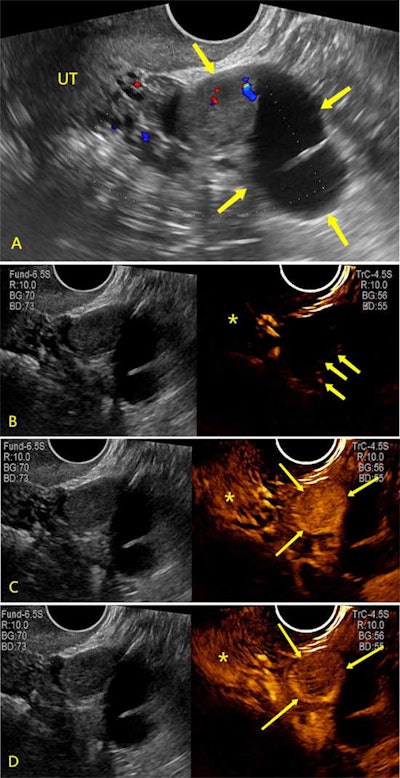

Ultrasound images show fallopian tube carcinoma in a 58-year-old woman. (A) Image shows a unilocular cyst with solid component (arrows) in the left adnexal area, which was categorized as O-RADS 4. UT = normal uterus. Color Doppler flow image shows minimal flow in the lesion. (B-D) Ultrasound (left) and CEUS images display the same plane simultaneously. (B, C) CEUS images show earlier enhancement (arrows) and higher enhancement intensity (arrows) in comparison with myometrium (*). CEUS shows earlier enhancement (arrows in B) and higher enhancement intensity (arrows in C) in comparison with myometrium (*). (C, D) Dynamic changes in CEUS from hyperenhancement to hypo-enhancement (arrows) compared with myometrium (asterisk) were observed. This lesion was upgraded to O-RADS CEUS 5 because the CEUS score was 5. Images and caption courtesy of RSNA.